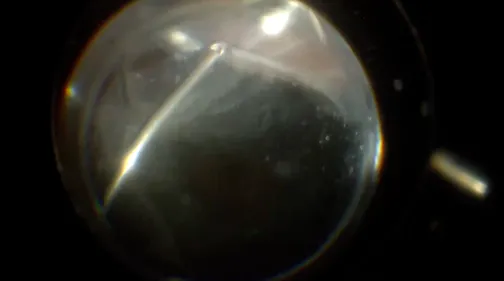

Ahmed Sallam, MD, and Riley Sanders, MD, present a case of a patient experiencing a dislocation of a three-piece IOL into the vitreous. The lens is removed and exchanged for an anterior chamber IOL.